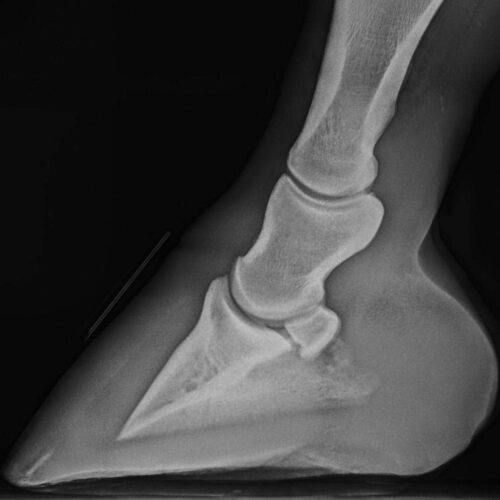

Verstehe den Innenfuß und lerne die Zusammenhänge zur Trachtenstütze und zur Sohle124,95 € inkl. MwSt.

Verstehe den Innenfuß und lerne die Zusammenhänge zur Trachtenstütze und zur Sohle124,95 € inkl. MwSt. -